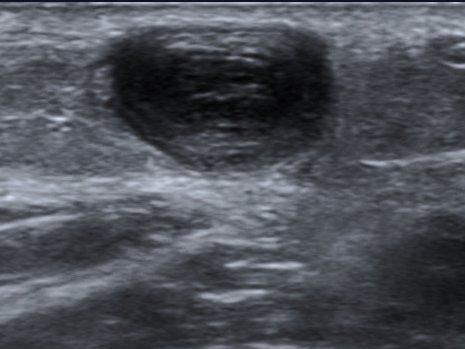

🟢 Test : Compression transversale

-

Appui perpendiculaire progressif

La veine normale s’écrase totalement

Si non compressible → TVP jusqu'à preuve du contraire

🧪 Signes directs de thrombose

Veine non compressible ± douleur à la compression

Visualisation d'un thrombus intraluminal

Absence de flux Doppler

Veine dilatée par rapport à l’artère